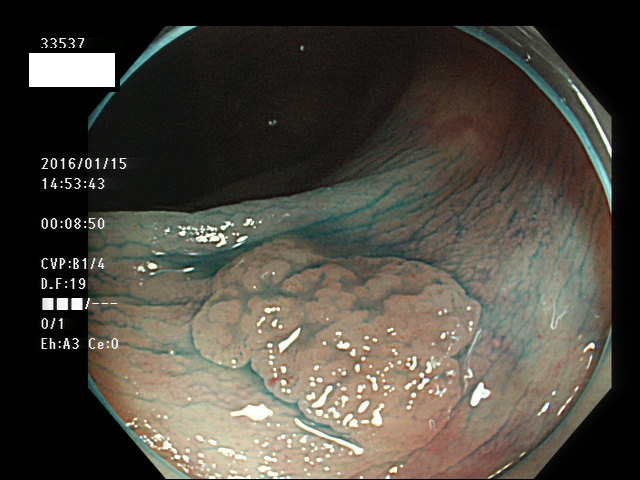

上記100名より抽出した平坦・陥凹型腺腫(=癌化の危険が高いが見落としやすい病変)の内視鏡写真

33500 33501 33505 33507 33508 33509 33510(SSA/Pのみ) 33511 33512 33514 33517 33519 33523 33528 33529 33530 33535 33537 33538 33539 33540 33544 33546 33547 33548 33549 33550 33552 33553 33555 33558 33559 33562 33563 33567 33571 33576 33578 33580 33581 33583 33585 33586 33587 33589 33590 33594 33595 33596 33599 ・・・・・・の50名